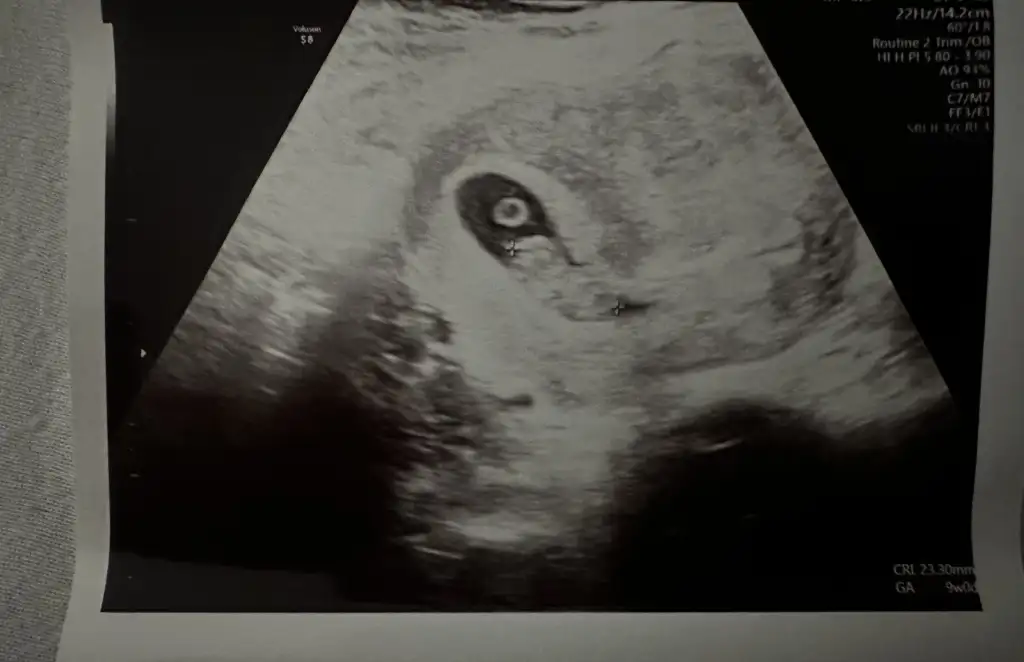

keseniz erkeğe benziyprCinsiyet belli olurmu kesenin şekline bakarak anlıyorlar ya kizlar yorum yapın bakalım ikinci hamilelik geçiren tecrübeli hamisler8+3 suanki kese

Teyzeler 7+5 olmuşuz çok şükür bugün kalp atışı duyduksizce cinsiyeti ne ?

sizin yuvarlak gıbı kıza benzıyorsemocann benimkine de bakar mısınız